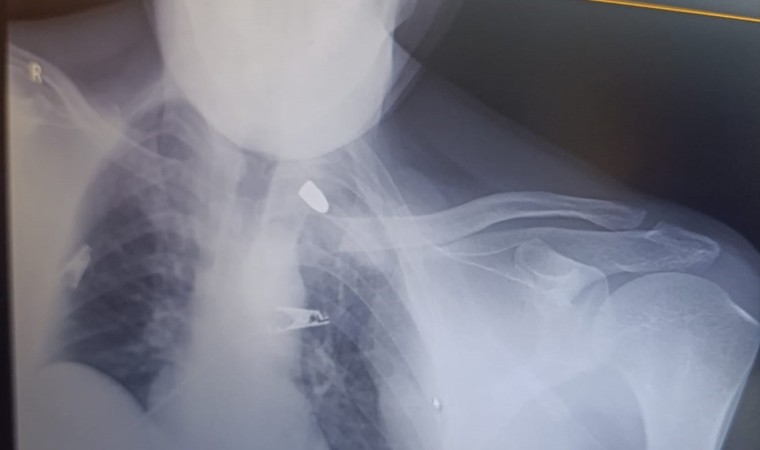

Olay, akşam saatlerinde Birecik ilçesine bağlı Karşıyaka Mahallesinde meydana geldi. İddiaya göre, damda uyuyan Sever Ataş’a (43), nereden ateşlendiği belirlenemeyen bir yorgun mermi isabet etti. Göğsüne isabet eden mermi ile yaralanan Ataş kanlar içerisinde kaldı. Olayı fark eden yakınlarının ihbarı ile ambulansla Birecik Devlet Hastanesi’ne kaldırılan Ataş, hayati tehlikesi bulunduğu gerekçesiyle Şanlıurfa Mehmet Akif İnan Eğitim ve Araştırma Hastanesine sevk edildi. Tedavisi devam eden adama isabet eden kurşunun göğsünde takılı kaldığı görüldü. Polis silahı ateşleyen kişinin tespit edilmesi için çalışma başlattı.